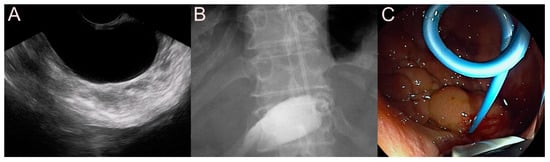

2.2. Stent for EUS-Guided Bile Duct (BD) Drainage

2.2.1. Use of the Plastic Stent

2.2.2. Use of the SEMS

2.2.3. Use of the LAMS